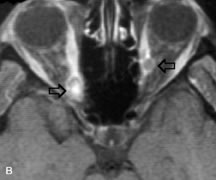

Breast carcinoma metastatic to the orbit has been demonstrated to be hypointense to the surrounding orbital fat on T1-weighted studies and hyperintense on T2-weighted images and has an affinity to the extraocular muscles (Fig. 20).50,64 The MRI characteristics of prostate carcinoma metastatic to the orbit have been described as involving the greater and lesser wing of the sphenoid, orbital roof, and optic canal. Diffuse bone hypertrophy with isointense or slightly hyperintense tissue on T1-weighted images represents the osteoblastic carcinomatous bone infiltration. Contrast enhancement is variable on T1-weighted and fat-suppressed images.65

Fig. 20. A. T1-weighted MR scan demonstrates nodular enlargement of both medial rectus muscles (arrows). B. T1-weighted fat-suppressed contrast-enhanced scan confirms the presence of small metnstatic deposits within the muscles (open arrows).